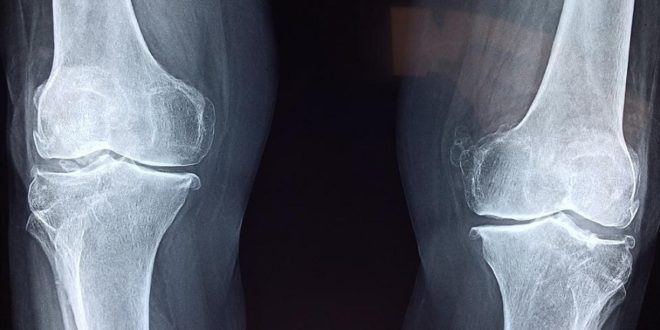

Pixabay License. Volné pro komerční užití

Již dnes se umělého kloubu dočká během života každý desátý Brit. S tím, jak populace stárne a také přibírá na váze, se tento podíl bude každopádně zvyšovat. Celosvětově umělý kloub dostane každoročně asi 5 milionů lidí a v příštích dvou desetiletí se toto číslo dle odhadů zdvojnásobí. Miliardy dolarů se vynakládají na vývoj kloubních náhrad s delší životností (inovace v oblasti konstrukce, materiálů…) a na optimalizaci zákroků pomocí robotických technologií.

Nejoblíbenějším materiálů pro umělé klouby (asi 70 % implantátů) je dnes slitina kobaltu a chromu. Když se malé částice CoCr při opotřebování kloubu uvolňují do krve, může to vyvolat imunitní reakci i bolest. To, že různí pacienti reagují na CoCr tak odlišně, podle nového výzkumu právě souvisí s geny. Podařilo se přímo stanovit genotyp, který je spojen se zvýšeným rizikem. Vědci vyvinuli pomocí strojového učení algoritmus Orthotype, který jako vstup dostane genom pacienta a na tomto základě odhadne pravděpodobnost přecitlivělosti na CoCr. Učení probíhalo na základě dat 606 pacientů, kteří byli sledováni v průměru 10 let.